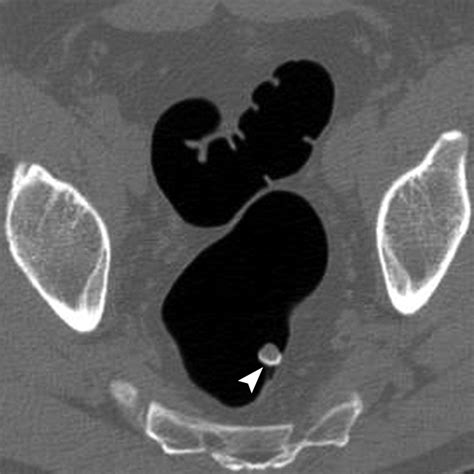

At its core, Ct Scan Colonography is a specialized radiological imaging test that produces 2D and 3D images of the large intestine. Unlike a standard colonoscopy, which involves physical exploration of the bowel, this procedure relies on computed tomography (CT) to create a detailed internal map. The process requires the patient’s colon to be inflated with air or carbon dioxide to ensure the walls of the bowel are fully distended, which allows the CT scanner to capture clear, unobstructed views of the lining.

• Inflation: A thin, small tube is placed just inside the rectum. Through this tube, air or carbon dioxide is gently pumped to inflate the colon, ensuring the entire surface is visible to the scanner.

However, it is important to acknowledge the limitations. The most notable limitation is that while the scan can identify suspicious polyps, it cannot remove them. If a polyp is detected during the scan, the patient will need to undergo a traditional colonoscopy to biopsy or remove the growth. Furthermore, because the scan utilizes ionizing radiation, it is generally recommended to discuss the cumulative exposure with a healthcare provider, especially if frequent screenings are anticipated over a lifetime.